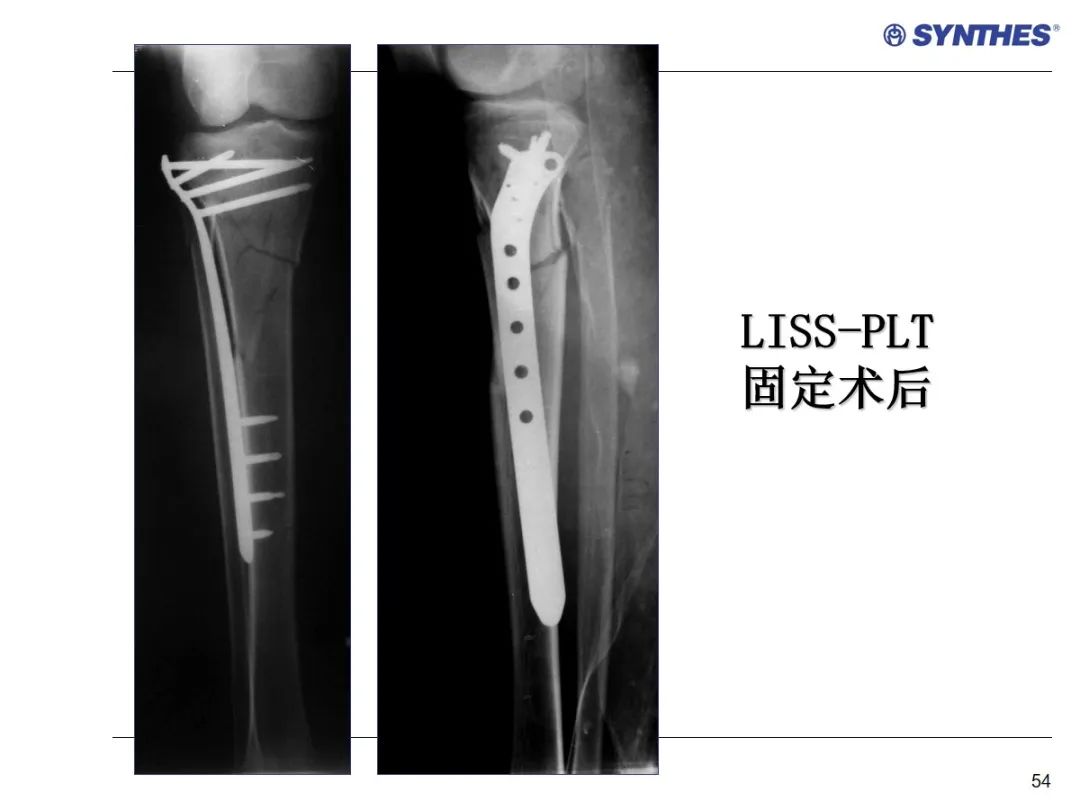

LISS微创固定系统应用技巧,原来如此简单!